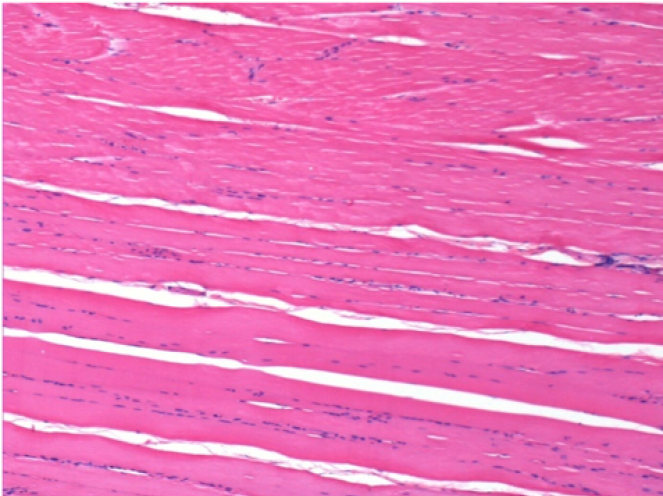

سبعة أشهر بعد حقن إندوبيل

7 أشهر (D210) بعد حقن Endopeel IM 0.1 مل في العضلة أمام الظنبوب اليمنى.

Complete Restitutio ad integrum after 7 months

L : Control-100xD210

R:100xD210

L :Control 50xD210

R50X-D210